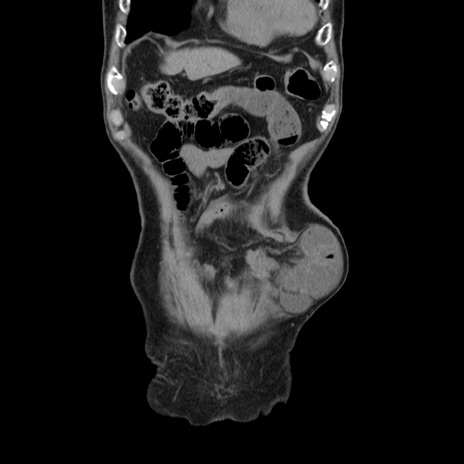

矢状断像

【症例】80歳代男性

【主訴】左側腹部痛、嘔吐

【現病歴】本日早朝より左腹部に痛みあり。昼頃嘔吐認めたため、救急要請。

【既往歴】直腸癌(Mile手術)、胆摘

【身体所見】意識清明、BT 35.9℃、BP 221/93mmHg、SpO2 97%(RA) 、腹部:左ストーマ周囲に限局性の腹部膨隆あり。 膨隆部自発痛・圧痛あり・軟。